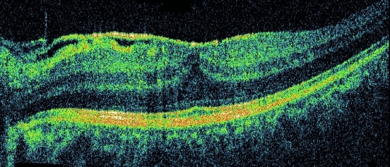

Η οπτική τομογραφία συνοχής (OCT) αποτελεί μια διαγνωστική εξέταση, η οποία δίνει κατευθυντήριες γραμμές για τη θεραπεία.

Εικόνα 3: Φυσιολογική εικόνα OCT αριστερά και με επιαμφιβληστροειδική μεμβράνη δεξιά.

Η αξιολόγηση της κάθε σάρωσης έχει υψηλή ευαισθησία έτσι ώστε να επιτρέπει την ανίχνευση ήπιων-ασυμπτωματικών αλλαγών, δίνοντας πληροφορίες για την πρόγνωση της νόσου.